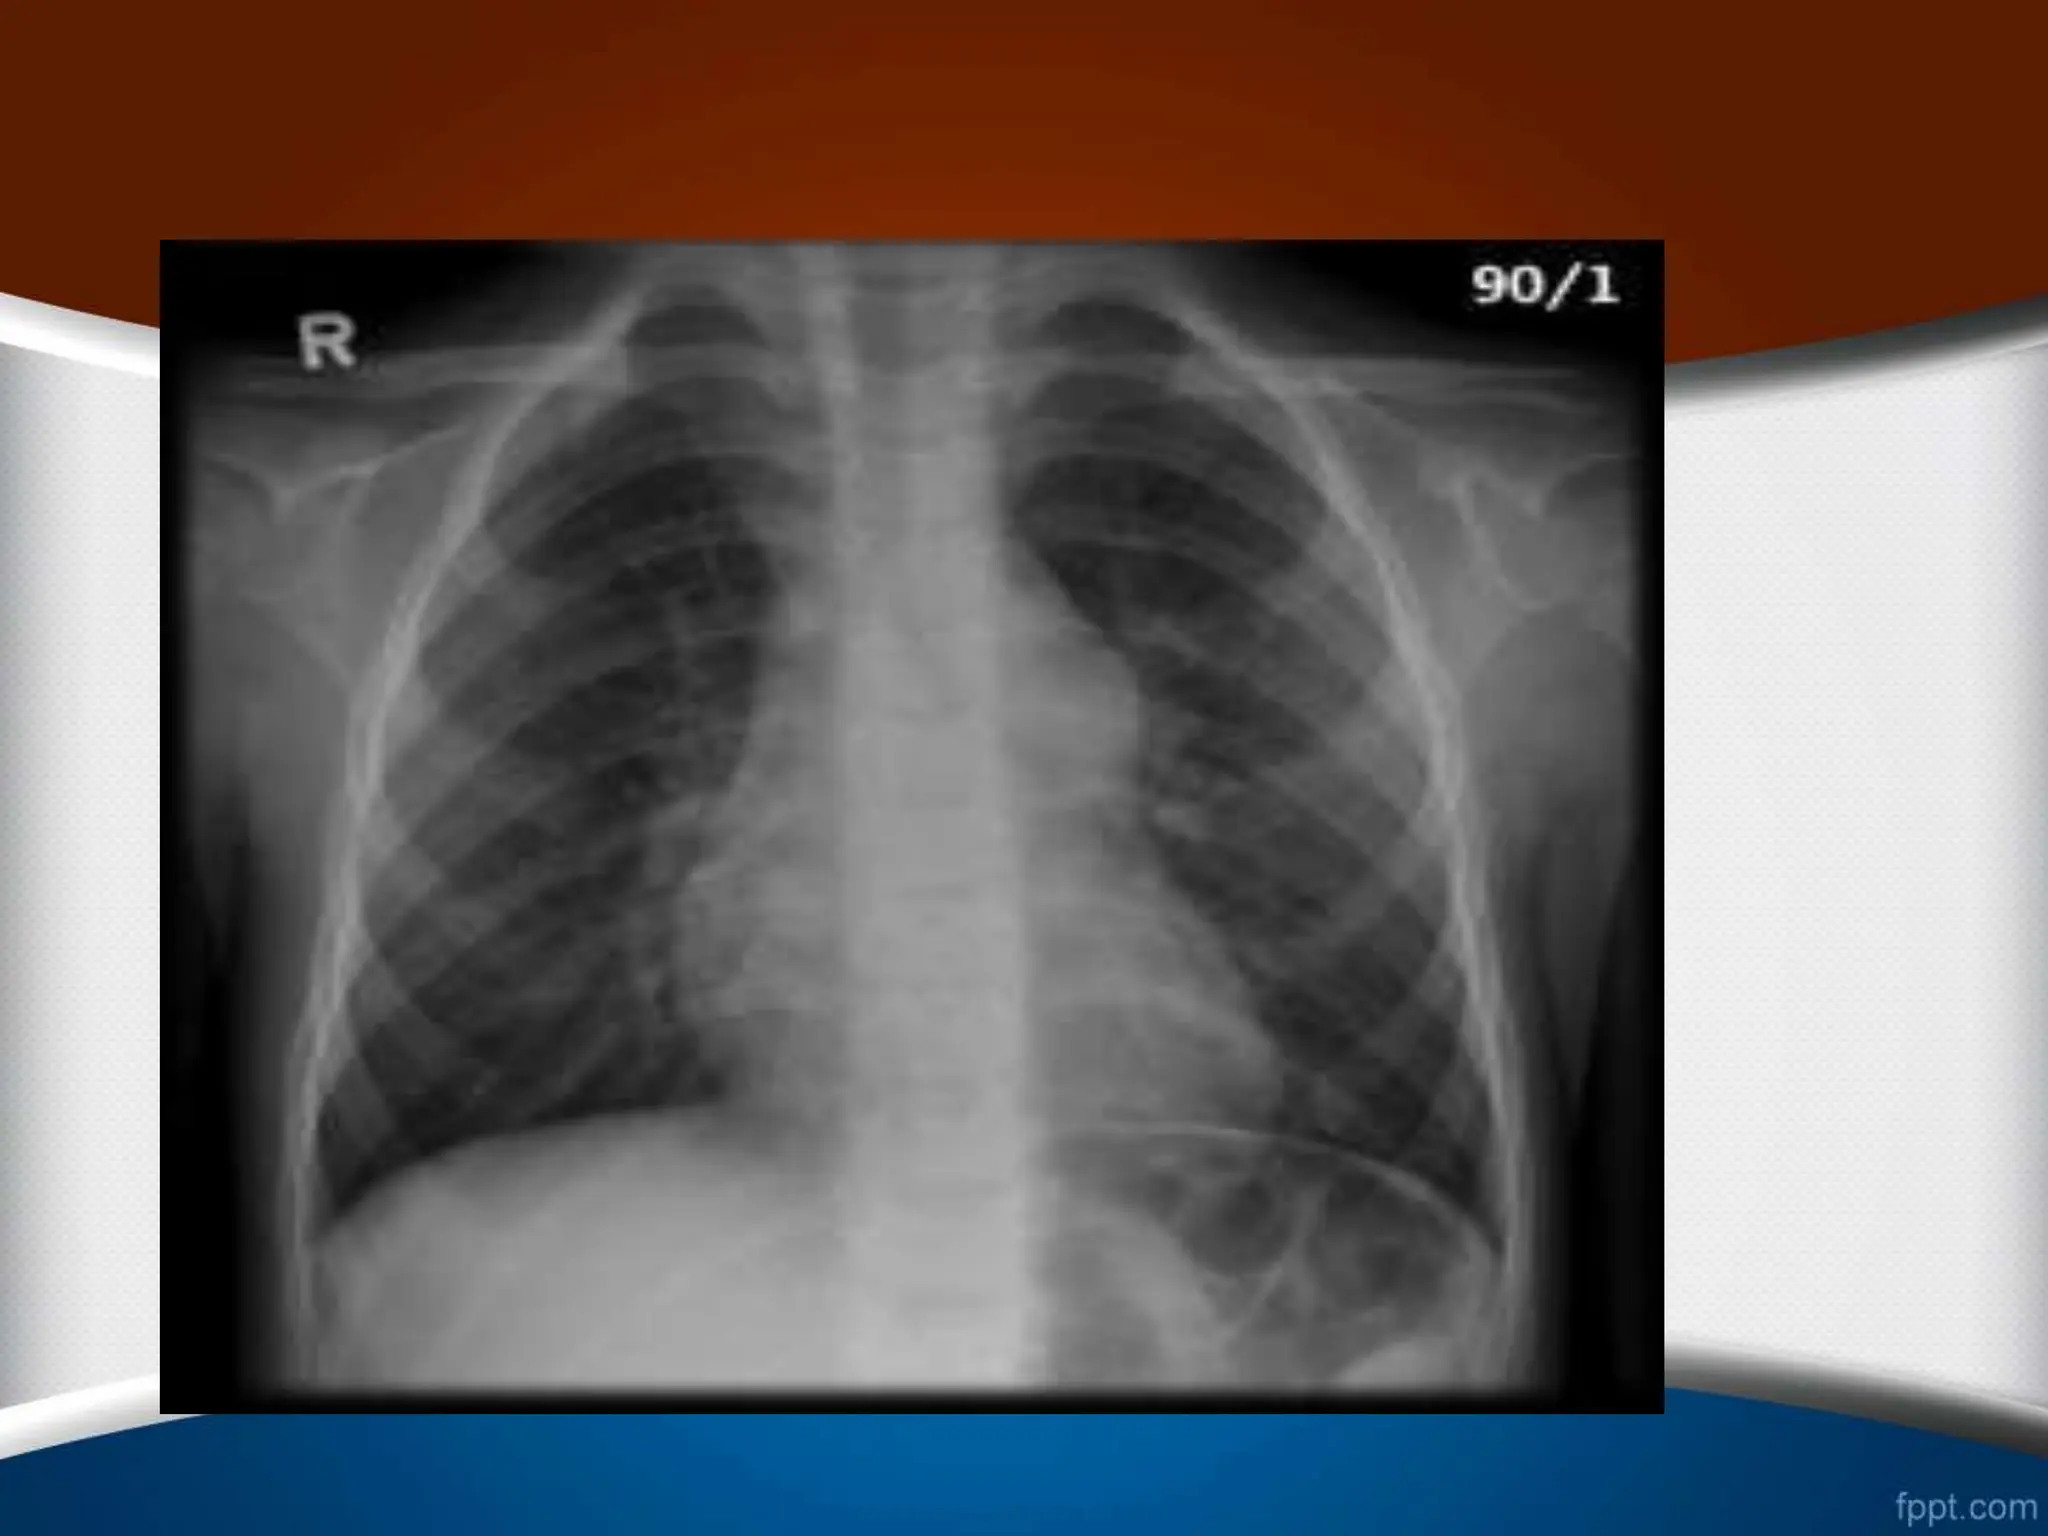

‫ریوی‬ ‫عروق‬ ‫نرمال‬ ‫طرح‬

.1

RDPA

‫از‬ ‫کمتر‬ ‫نرمال‬ ‫خانم‬ ‫فرد‬ ‫در‬

16

‫آقای‬ ‫در‬ ‫و‬ ‫متر‬ ‫میلی‬

‫از‬ ‫کمتر‬ ‫نرمال‬

18

‫متر‬ ‫میلی‬

.2

‫در‬

1/3

‫رادیوگرافی‬ ‫در‬ ‫نرمال‬ ‫فرد‬ ‫یک‬ ‫در‬ ‫ریه‬ ‫محیط‬

PA

‫طرح‬

‫شود‬ ‫نمی‬ ‫دیده‬ ‫عروقی‬

.

.3

‫شریان‬ ‫سایز‬ ‫نسبت‬

(

A

)

‫برونش‬ ‫به‬

B

‫یعنی‬

A/B

‫ریه‬ ‫قله‬ ‫در‬

‫های‬

85

%

‫نسبت‬ ‫این‬ ‫ریه‬ ‫ی‬ ‫قاعده‬ ‫در‬ ‫و‬ ‫یک‬ ‫ریه‬ ‫ناف‬ ‫در‬ ‫و‬

35/1

‫است‬